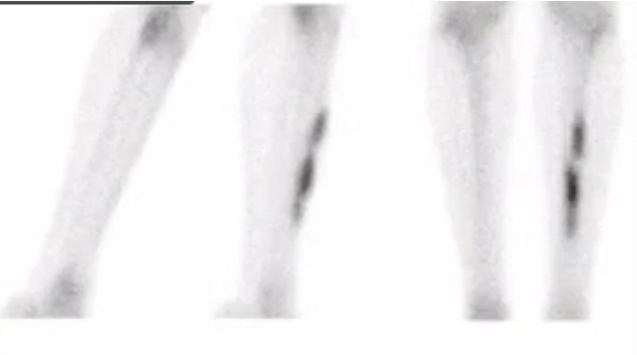

how long do you have to be on bisphosphonates before you get insuffiency fractures?

4 years